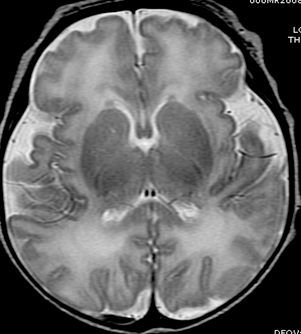

Blüml and colleagues have been studying preterm infants to learn more about how premature birth might cause changes in brain structure that may be associated with clinical problems observed later in life. Much of the focus has been on the brain's white matter, which transmits signals and enables communication between different parts of the brain. While some white matter damage is readily apparent on structural magnetic resonance imaging (MRI), Blüml's group has been using magnetic resonance spectroscopy (MRS) to look at differences on a microscopic level.

In this study, the researchers compared the concentrations of certain chemicals associated with mature white matter and gray matter in 51 full-term and 30 preterm infants. The study group had normal structural MRI findings, but MRS results showed significant differences in the biochemical maturation of white matter between the term and preterm infants, suggesting a disruption in the timing and synchronization of white and gray matter maturation. Gray matter is the part of the brain that processes and sends out signals.